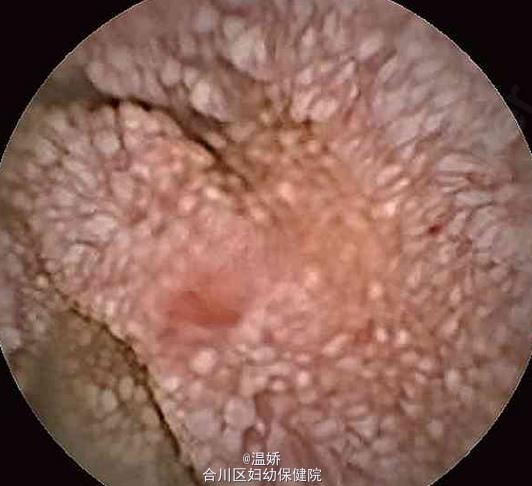

小肠淋巴管扩张 肠淋巴管扩张

患者男性,45岁。因“腹胀、腹泻伴下肢浮肿2个月”入院。

综合患者的临床表现、实验室检查、内镜下表现及活检病理结果,诊断为小肠淋巴管扩张症。 给予低脂饮食、补充白蛋白及利尿、补充肠道有益菌等治疗后,患者腹泻症状有所缓解。复查胸部CT示右侧胸腔积液明显减少,右肺尖见一钙化灶,考虑陈旧性肺结核可能。告诉患者该病预后较差,嘱其出院后改善饮食结构,注意补充日常所需能量,加强随访。